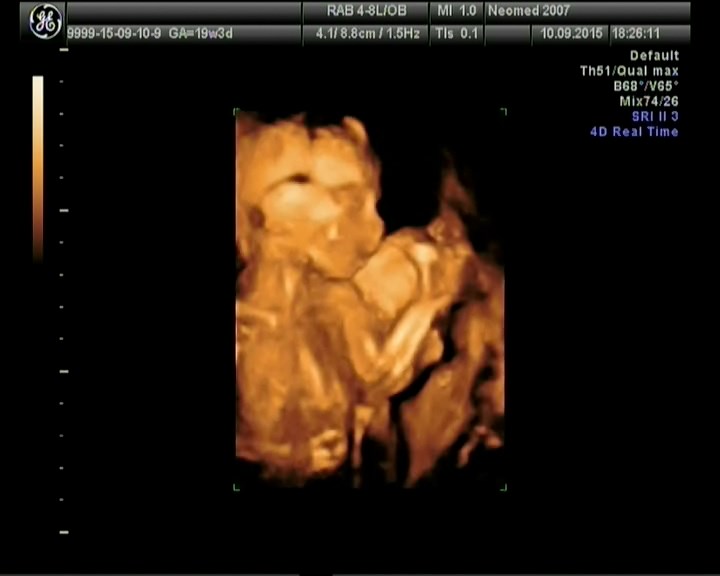

ну и конечно же не могу не поделиться снимками как из фильмов ужасов в 4д)

Счастье, что все хорошо)))) Поздравляю))))))) Обхохоталась с Вашей фразы про фото из фильма ужасов. Моей дони тоже такое фото жуткое сделали, я не то что кому-то показать, сама на него смотреть боюсь)))))))

я маме видео показала,говорит может ты больше не будешь показывать мне такие ужасы)))